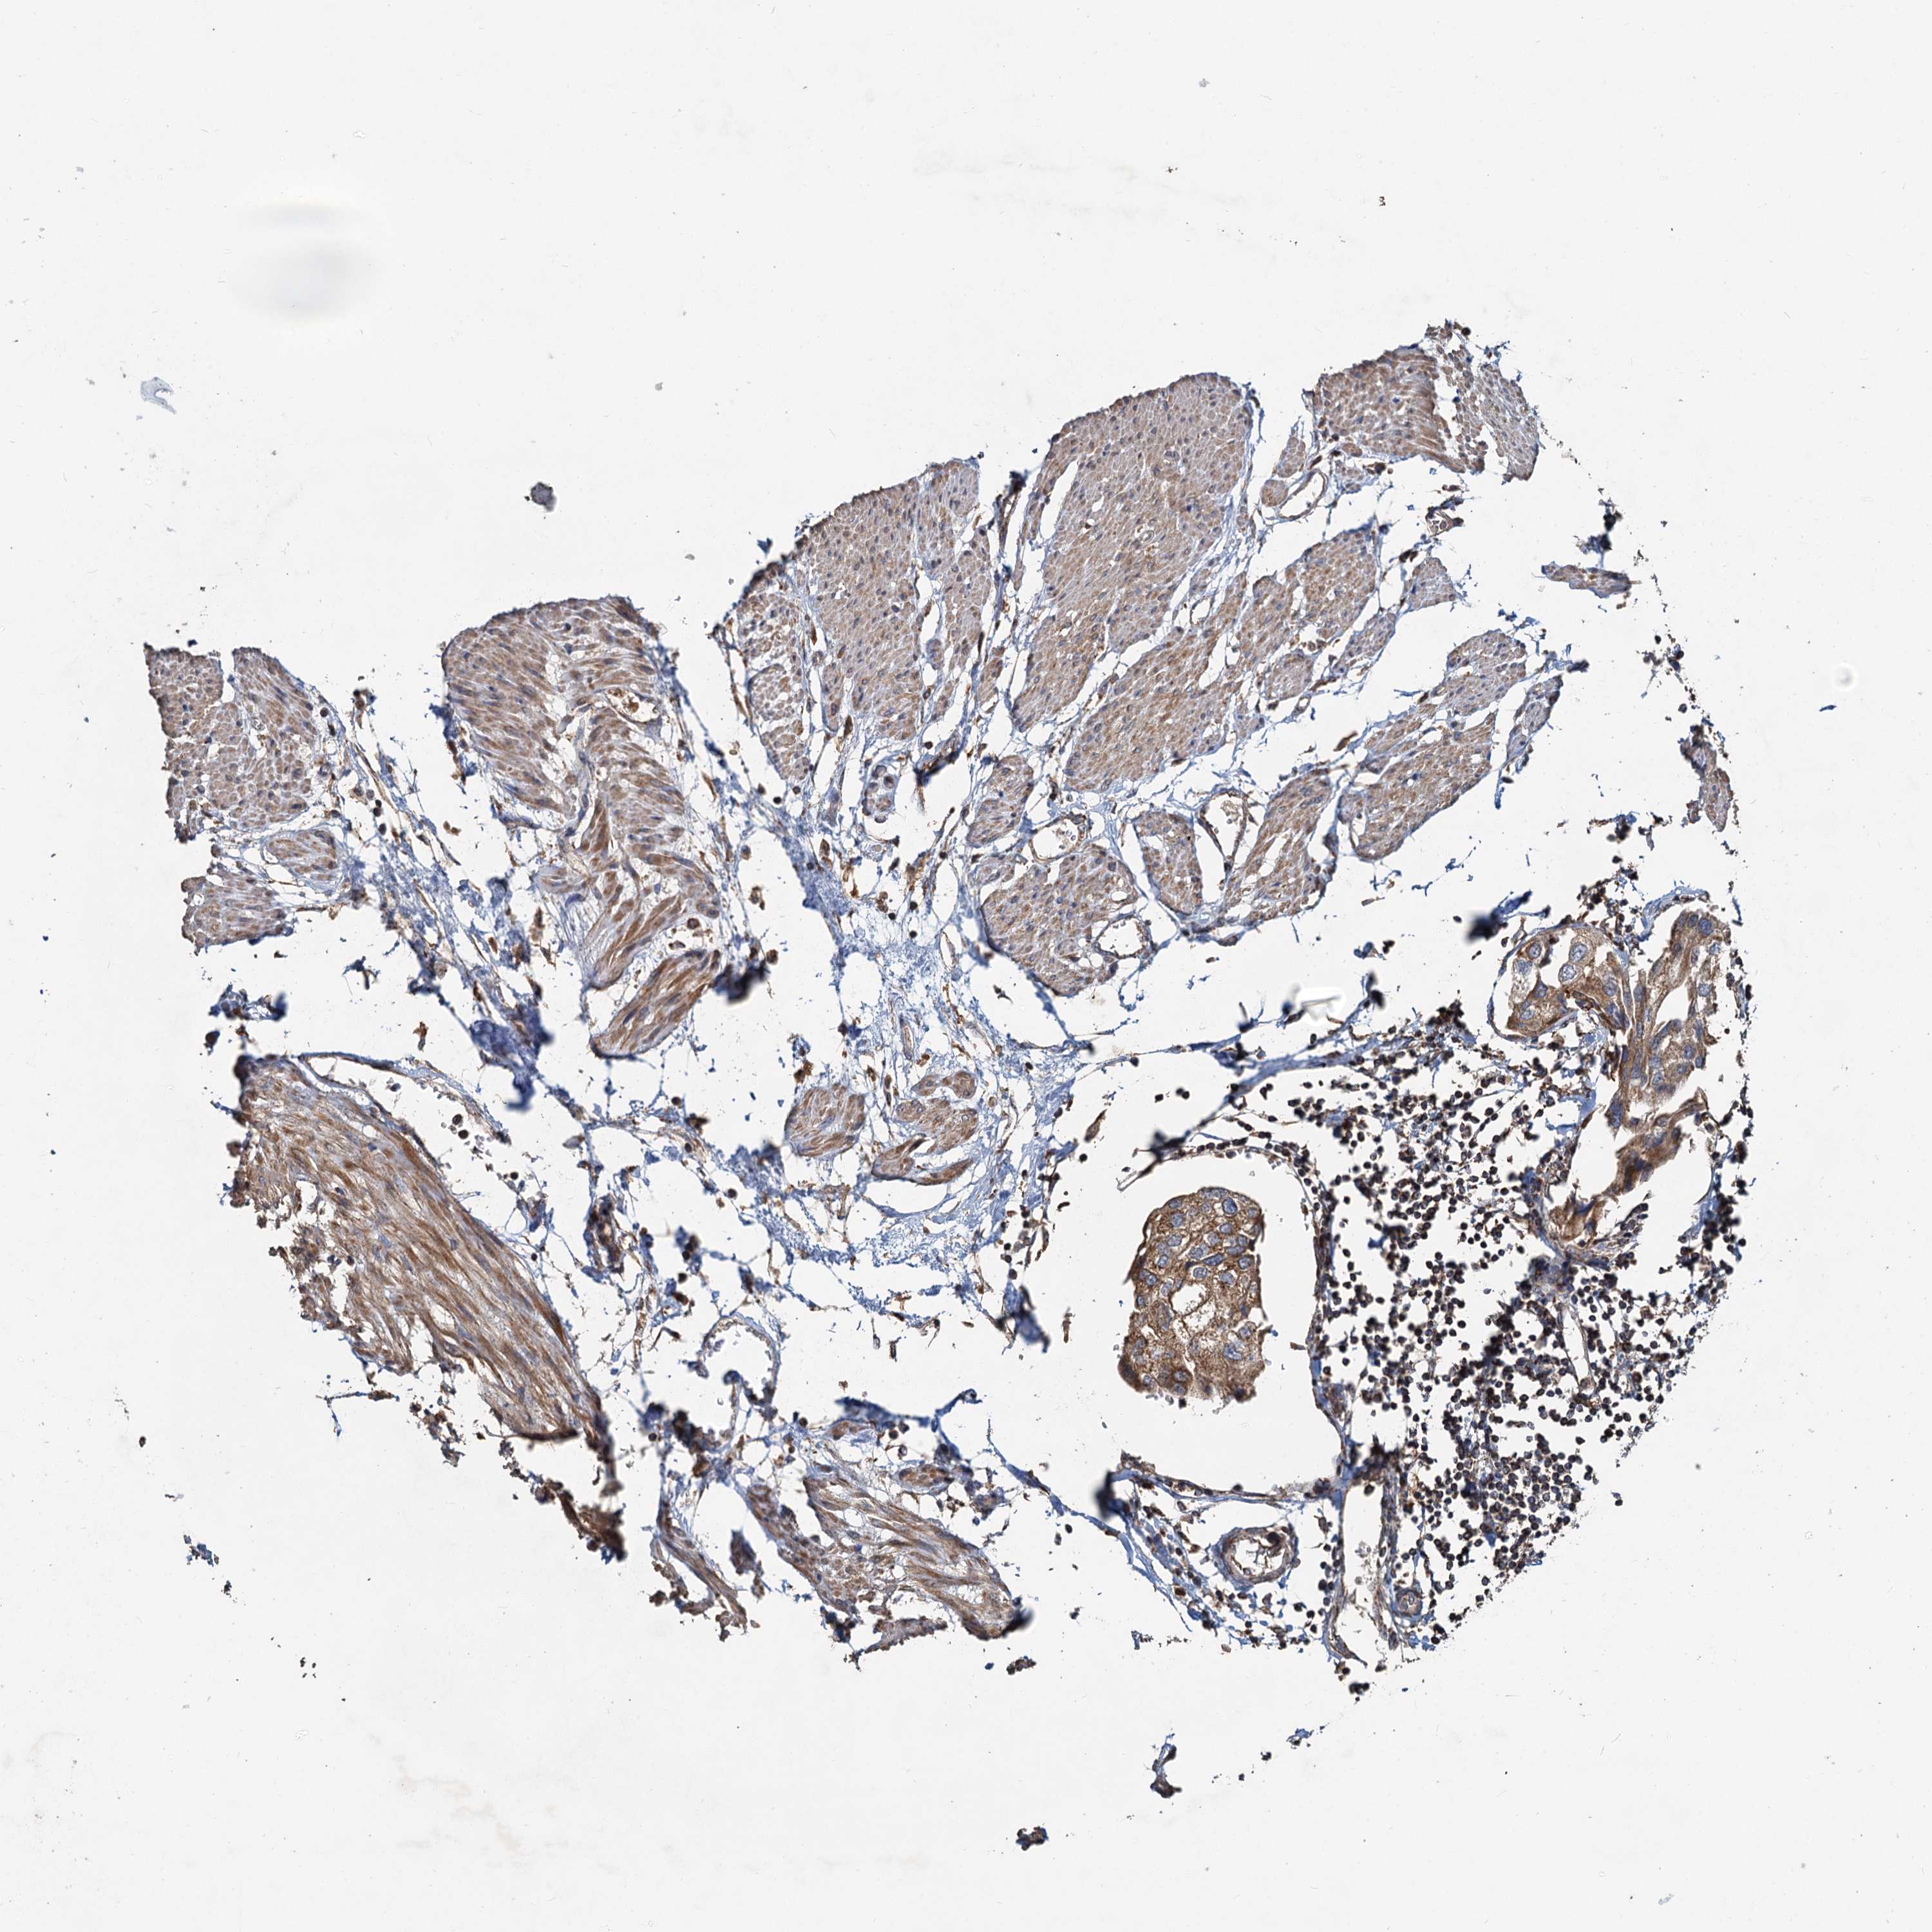

UROTHELIAL CANCER - Protein expressioni

A mouse-over function shows sample information and annotation data. Click on an image to view it in a full screen mode. Samples can be filtered based on level of antibody staining by selecting one or several of the following categories: high, medium, low and not detected. The assay and annotation is described here.

Note that samples used for immunohistochemistry by the Human Protein Atlas do not correspond to samples in the TCGA dataset.

Antibody stainingi

Antibody staining in the annotated cell types in the current human tissue is reported as not detected, low, medium, or high, based on conventional immunohistochemistry profiling in selected tissues. This score is based on the combination of the staining intensity and fraction of stained cells.

Each image is clickable and will lead to virtual microscopy that enables deeper exploration of all samples and also displays staining intensity scores, fraction scores and subcellular localization as well as patient and tissue information for each sample.

Antibody HPA039230

Staining

High

Medium

Low

Not detected

Intensity

Strong

Moderate

Weak

Negative

Quantity

>75%

75%-25%

<25%

None

Location

Nuclear

Cytoplasmic/membranous

Cytoplasmic/membranous,nuclear

Urothelial carcinoma, High grade

Urothelial carcinoma, NOS